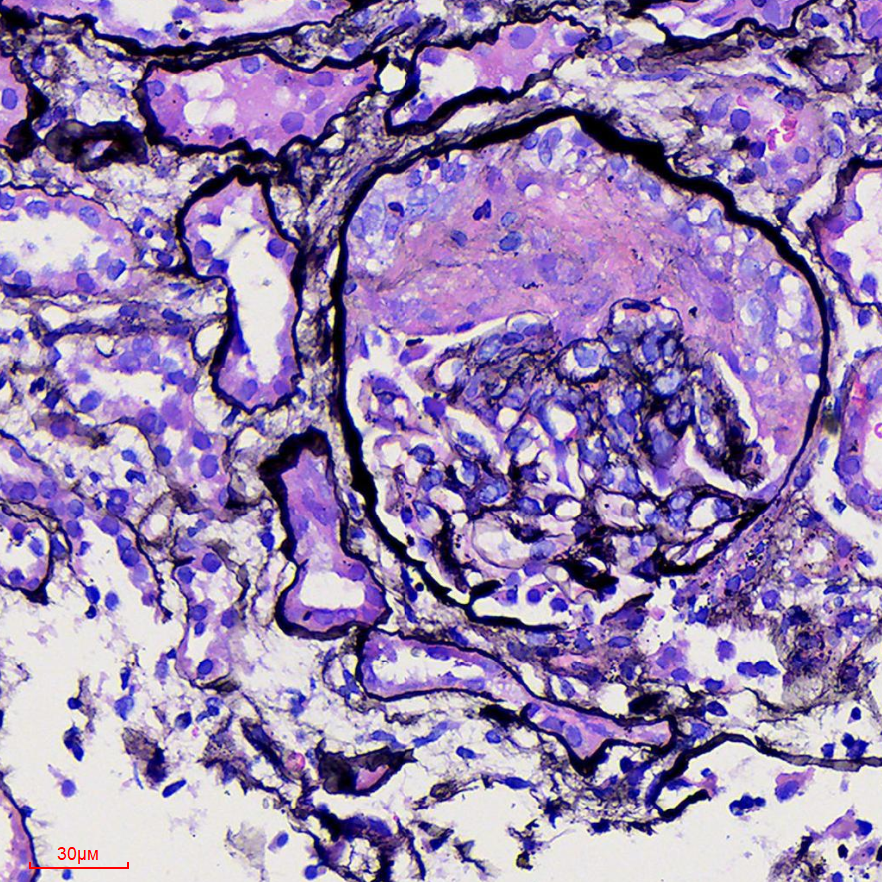

诊疗团队经过仔细的排查、多次讨论和查房,并与病理科陈虹主任医师、陶璇主治医师讨论肾脏病理改变后,考虑为过敏性紫癜合并免疫复合物介导的II型新月体肾炎

医讯怎么用『附一医讯』乱用偏方致过敏,女子急性肾衰竭!福建医大附一医院肾内科“换血救肾”_https://www.jmylbn.com_新闻资讯_第8张

▲肾小球新月体形成肾小管坏死

医讯怎么用『附一医讯』乱用偏方致过敏,女子急性肾衰竭!福建医大附一医院肾内科“换血救肾”_https://www.jmylbn.com_新闻资讯_第9张

▲肾小球新月体形成并间质有炎症细胞浸润